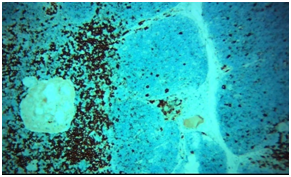

Microscopic picture

In multiple bits of the tissue received, multiple cystic spaces are seen, some are rounded others are irregular. Cysts lining ranged from the cubical stratified epithelium. Other cysts form a fibrous capsule. Cysts are filled with huge numbers of multinucleated gains cells and large numbers of cholesterol crystals. Outskirts show multiple foci of thymus gland tissue with a well-formed cortex of packed, monotonous lymphoid T-cells, with tangible body macrophages. Medulla show less packed lymphoid cells. Epithelial whorls of Hassall’s corpuscles are evident. Fibrocollagenous tissue surrounding the cysts show congested capillaries. No evidence of Malignancy.